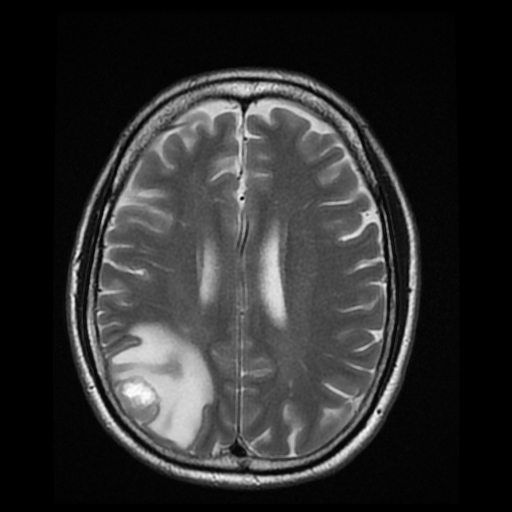

Patients with brain tumors may complain symptoms of headache, dizziness, vomiting, blurred vision, limbs weakness, etc.. Other symptoms include seizures and endocrine disorders; Personality or behavior changes may also occur. With modern advances in brain imaging technology, Computerized Tomography (CT) scan and magnetic resonance imaging (MRI) are the most commonly used diagnostic tools.

MRI does not involve radiation risk. Patients are required to lie inside the scanner with a strong magnetic field. Patients will not feel pain during the scanning process. MRI images can be achieved in a number of different angles and through a variety of different "signals", so as to letting us to explore more about the tumors’ nature, thus allowing neurosurgeons making the most appropriate treatment plan for patients.